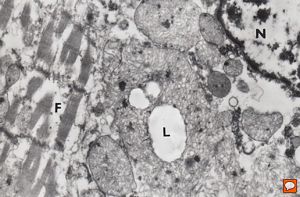

normal cardiomyocyte … longitudinal section(m … mitochondrion, f - myofilaments, L … lipid droplets, arrows … tubulesof sarcoplasmic reticulum)